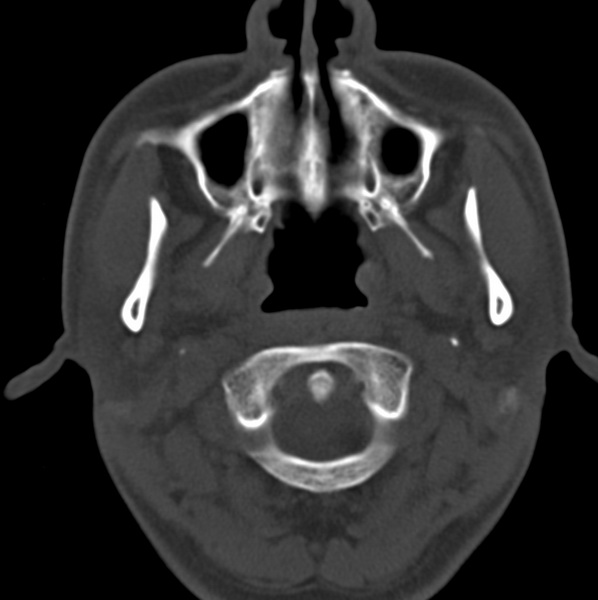

男、31、鼻咽部肿瘤放疗后请帮忙看看。

效果好,右侧破裂孔扩大,局部骨质缺损,为颅底骨质破坏。

1)鼻咽部肿瘤侵犯颅底放疗术后改变。2)左侧蝶窦炎。

咽后壁增厚,左侧咽鼓管隆突增大、咽鼓管咽口变浅,同侧咽旁间隙较窄。右侧颅底骨质破坏?为什么不在同一侧?

鼻咽部肿瘤侵犯颅底放疗术后改变.